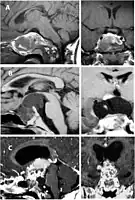

Imaging scans for craniopharyngioma

A physician can conduct a few scans and tests to diagnose a person with craniopharyngioma.[19] High-resolution magnetic resonance imaging (MRI) is valuable because it allows the neuroradiologist to view the tumor from different angles.

In some cases, a powerful 3T (Tesla) MRI scanner can help define the location of critical brain structures affected by the tumor. The histologic pattern consists of nesting of squamous epithelium bordered by radially arranged cells. It is frequently accompanied by calcium deposition and may have a microscopic papillary architecture. A computed tomography (CT) scan is also a good diagnostic tool, as it detects calcification in the tumor.[20]